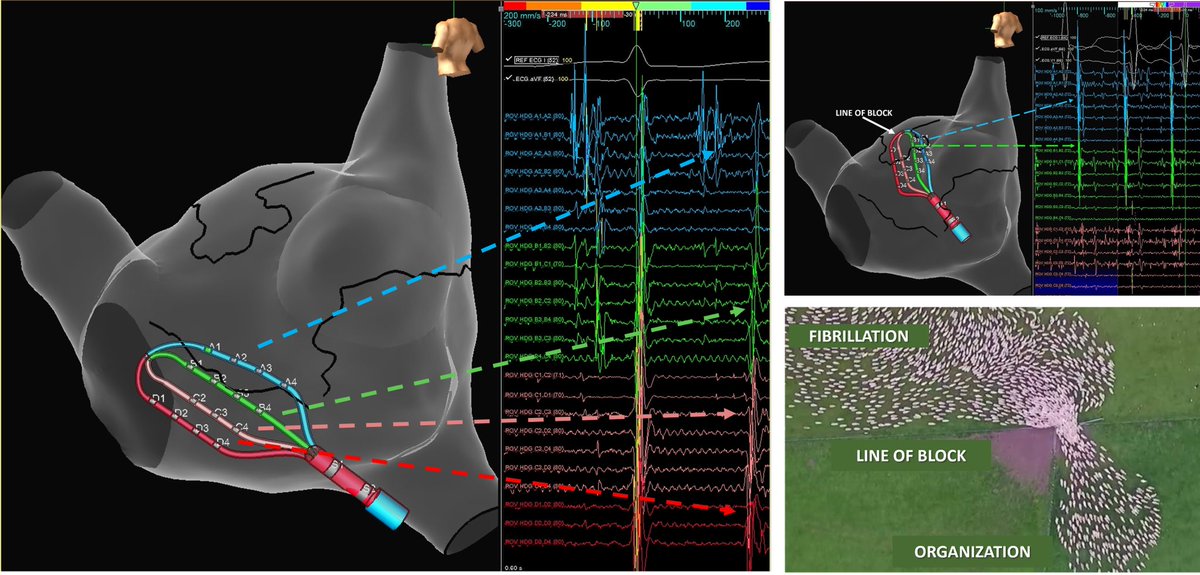

Lines of block from regions of scar organize AF into flutter-like bystander rhythm in the RA. Note the decreasing complexity as the splines approach the funnel point. Interesting observation to apply to our AF interpretation. #AbbottAF #HDGrid #MidAmericaEP @AbbottCardio